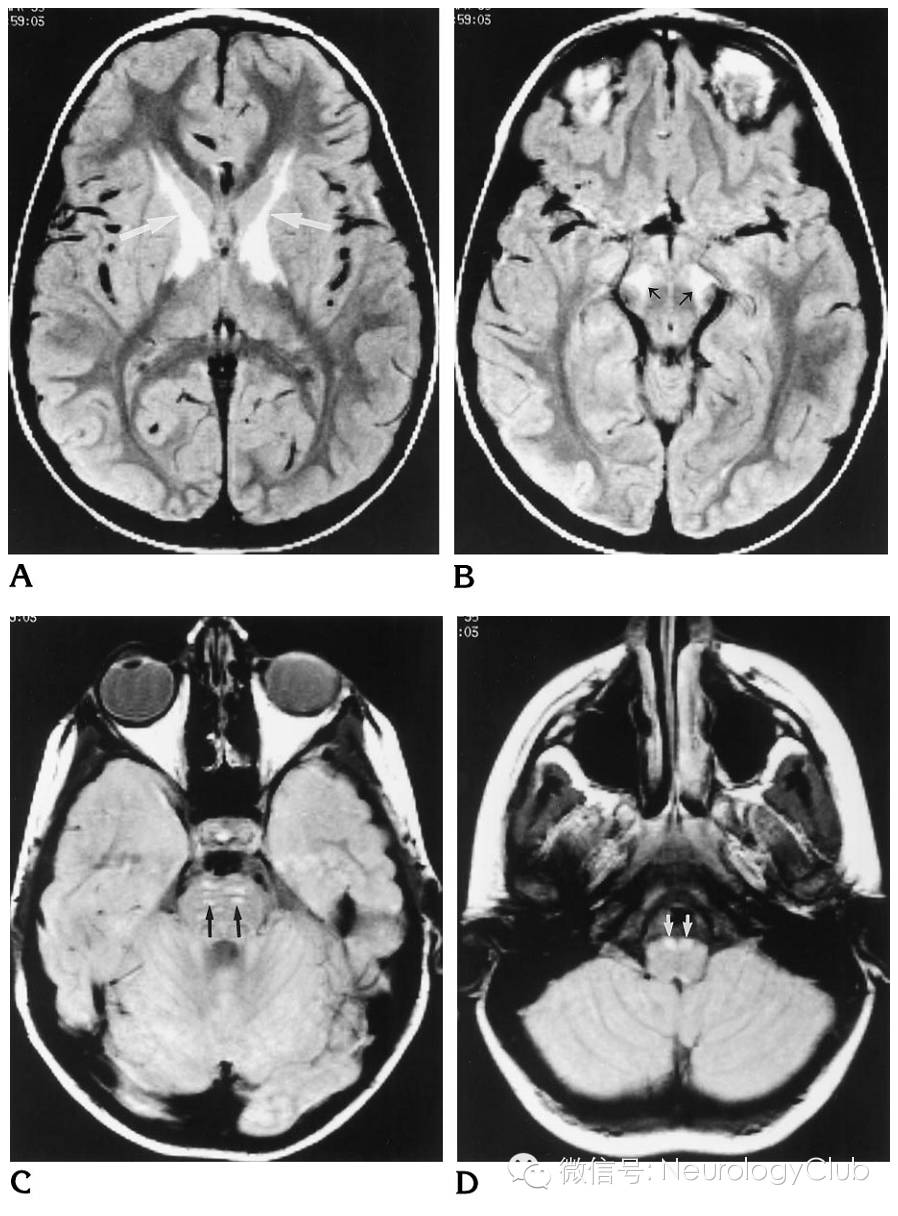

(7岁男孩,学习成绩下降。A:FLAIR提示内囊前肢,膝部,后肢前部高信号病灶,枕叶白质未受累;B:FLAIR提示大脑脚中部,即皮质脊髓束高信号;C:FLAIR提示双侧皮质脊髓束高信号;D:FLAIR提示延髓锥体高信号)